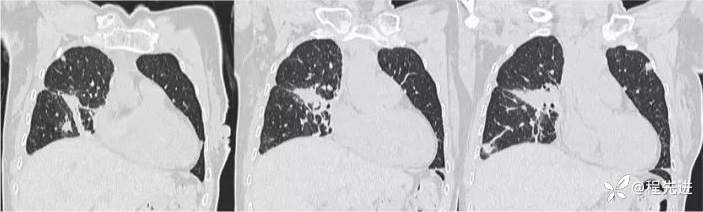

肺窗

肺窗冠状位重建